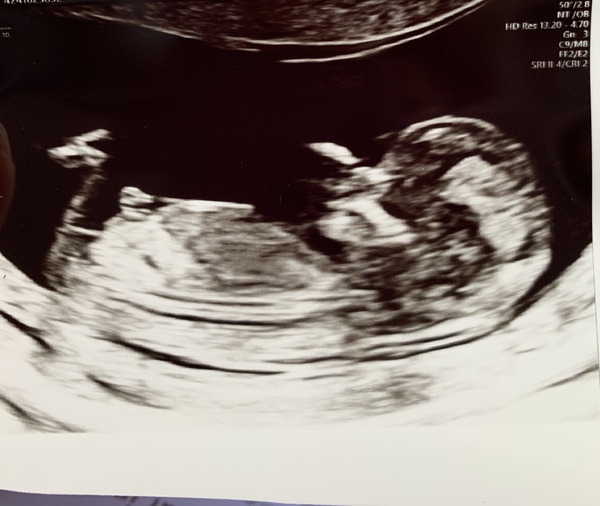

I feel like everyone’s scan pic is MUCH clearer than mine... I’m sure mine is too rubbish for there to be any chance of working out if it’s a girl or a boy, though maybe I’m just crap at reading them. Attaching in case anyone has any opinions!

BFP - Anyone else feb 2020? Continued ...